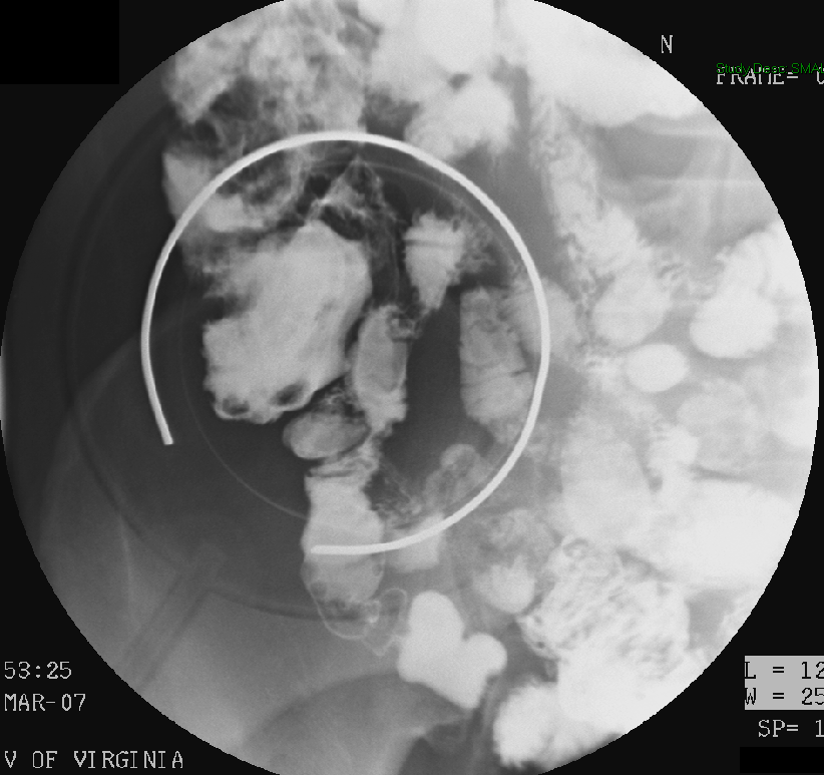

- When reviewing the preliminary scout film, you should see multiple surgical chain sutures in the pelvis

(key image 31)

(key image 32).

- After the enema tip has been placed but before contrast material has been administered, obtain a fluoroscopic spot film of the rectum with the patient in the left lateral position

(key image 33).

- As you instill contrast material into the J pouch, obtain images of the pouch and ileoanal anastomosis fully distended with contrast material in each of the following four (4) positions:

- left lateral

(key image 34)

- left posterior oblique

(key image 35)

- supine (AP)

(key image 36)

- right posterior oblique

(key image 37).